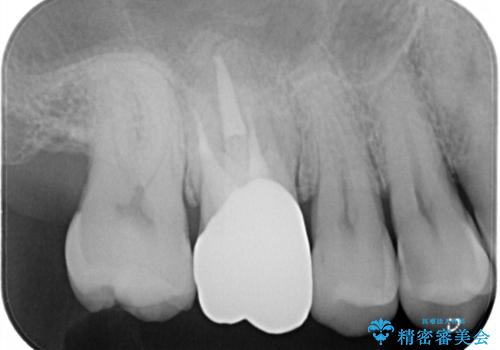

腫れもなくなり、見た目もきれいになったため、右上もご希望されて計3本の歯を治療しました。患者様には大変満足して頂きました。

左上で効果を実感して頂き、その後右上もご希望されました。合計3本の歯を治療しました。